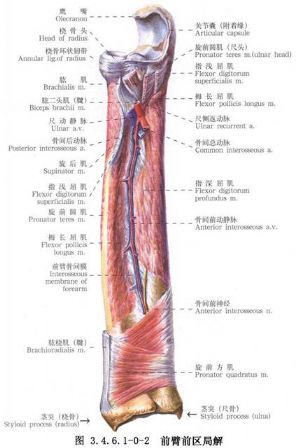

尺桡骨干骨折常见。由于暴力的原因和受伤瞬间肢体的姿式以及肌肉收缩的状态不同,可以发生尺桡骨干双骨折或单骨折。其中,又可发生于不同平面。尺骨干上1/3骨折合并桡骨小头脱位(孟氏骨折Montaggia fracture)。桡骨干下1/3骨折合并下尺桡关节脱位(盖氏骨折Galeazzi fracture)。其中尺桡骨干双骨折占全身骨折的5.41%,为第3位。桡骨骨折占4.23%,为第5位。尺骨骨折占1.05%,为第17位。孟氏骨折占0.63%,为第38位。盖氏骨折占0.35%,为第50位。由于前臂具有旋转功能,一旦发生骨折,除重叠和侧方移位外,尚有严重的旋转移位。因此,对复位的要求较高。如手法复位不满意,难以达到预期功能的恢复,即有手术复位的指征。相关解剖及影像表现见下图(图3.4.6.1-0-1~3.4.6.1-0-6)。